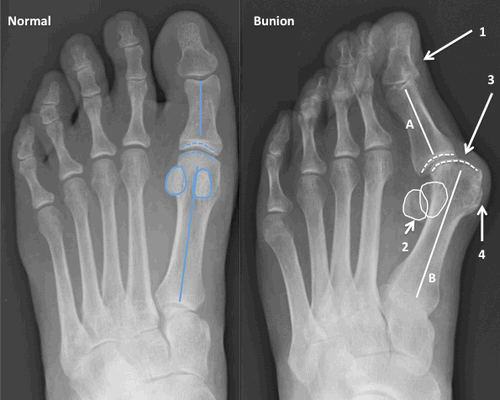

Различают несколько стадий hallux valgus которые отличаются как клинической картиной так и требованиями к тактике лечения.

Первая стадия hallux valgus чаще всего проявляется только изменениями на 1 луче стопы (первой плюсневой кости и 1 пальце). На этой стадии происходит небольшое отклонение 1 плюсневой кости кнутри (межплюсневый угол менее 13 градусов) и соответствующим отклонением 1 пальца кнаружи (угол вальгуса менее 25 градусов). На первой стадии пациентов беспокоит формирование "косточки" по внутренней поверхности головки 1 плюсневой кости, которое может приводить к бурситу- воспалению подкожной синовиальной сумки. На этой стадии пациенты чаще хотят просто избавиться от косточки, и не готовы к радикальному хирургическому лечению, так как после него следует длительный реабилитационный период. По сути это косметическое вмешательство, которое состоит из резекции костного экзостоза в обалсти головки 1 плюсневой кости, бурсэктомии, пластики суставной капсулы.

На второй стадии Халюс Вальгус происходит дальнейшее отклонение 1 плюсневой кости кнутри (межплюсневый угол 13-15 градусов) и кверху с дальнейшим увеличением угла вальгуса (26-40 градусов). На этой стадии также возможно вовлечение 2-3-4-5 лучей стопы. За счёт постепенного распластывания поперечного свода 5 плюсневая кость начинает отклоняться кнаружи, а 5 палец при этом смещается кнутри, картина зеркальная деформации 1 луча. 2-3-4 плюсневые кости при этом постепенно начинают опускаться вниз. Это приводит к их перегрузке, которая может провляться болями и формированием "натоптыша" под головками 2-3 плюсневых костей.

При планировании оперативного пособия выполняются рентгенограммы в прямой и боковой проекции. Производится расчёт углов вальгусного отклонения 1 пальца, угол между 1 и 2 плюсневыми костями, угол артикуляции 1 плюсневой кости. Исходя из рассчитанных углов, выбирается оптимальный метод остеотомии для коррекции имеющейся деформации.